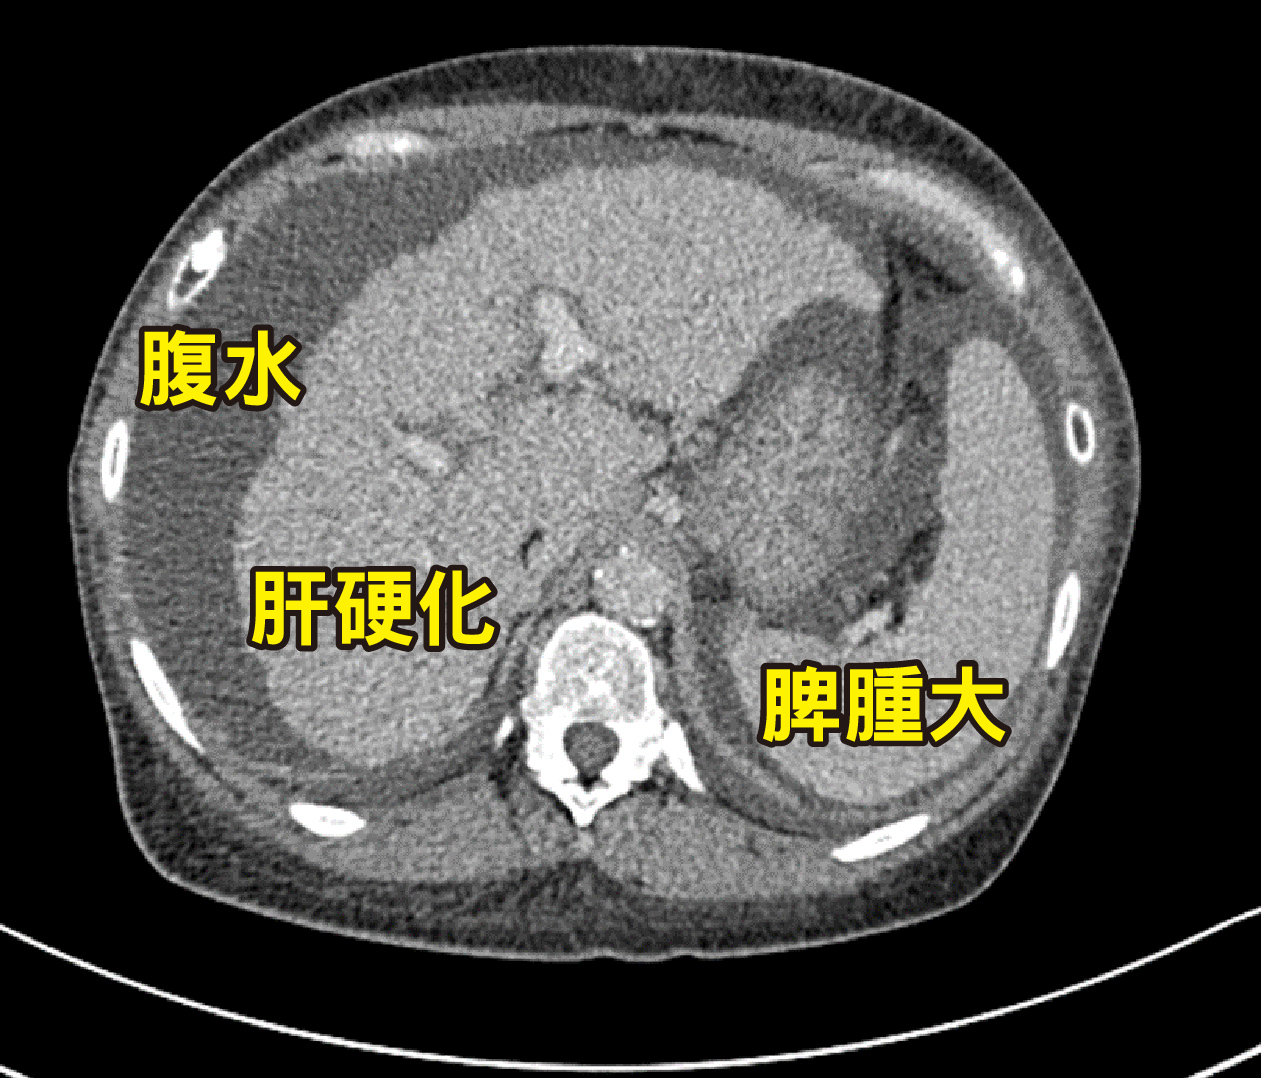

▲右圖、米德莉腹部電腦斷層掃描顯示肝臟已出現嚴重的「肝硬化」現象,並伴隨明顯的「腹水」蓄積以及「脾腫大」。

馬偕紀念醫院外科部副主任林俊昌表示,原發性膽汁性膽管炎(PBC)是一種慢性進行性自體免疫疾病,目前醫療無法根治,免疫細胞會破壞肝臟中的小膽管,形成膽汁淤積、發炎,若病人對藥物治療反應不佳,最終將導致肝纖維化與肝硬化;根據統計,因罹患PBC而需要肝臟移植者,約占全臺肝臟移植個案的一至二成;以米德利為例,病程已達重度肝硬化的C級,長期門脈高壓導致腹腔內側支循環異常發達且代償性擴張,加上肝功能衰竭引發的凝血因子合成障礙,使得術中極易發生大出血的高風險,致使移植手術更加困難,因此,在術前評估時,團隊嚴陣以待務必做好萬全的準備。